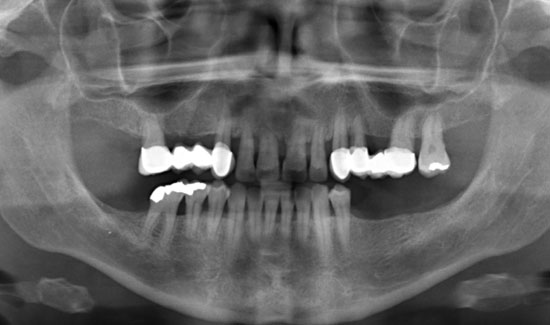

Abb. 1: Orthopantomogramm